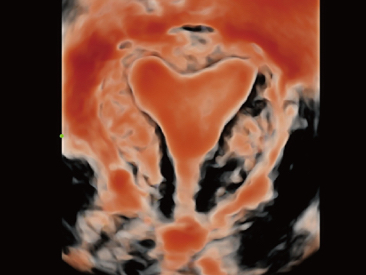

Selain kualitas gambar premium, Resona 7 juga meningkatkan kemampuan penelitian klinis dengan V Flow revolusioner untuk evaluasi hemodinamika vaskular, serta pengambilan penampang tercanggih dari rangkaian data 3D untuk diagnosis CNS pada janin. Kombinasi pengoperasian multisentuh berbasis gerakan yang paling intuitif dengan semua fitur klinis penting membuat Resona 7 menjadi gebrakan baru dalam inovasi ultrasound.